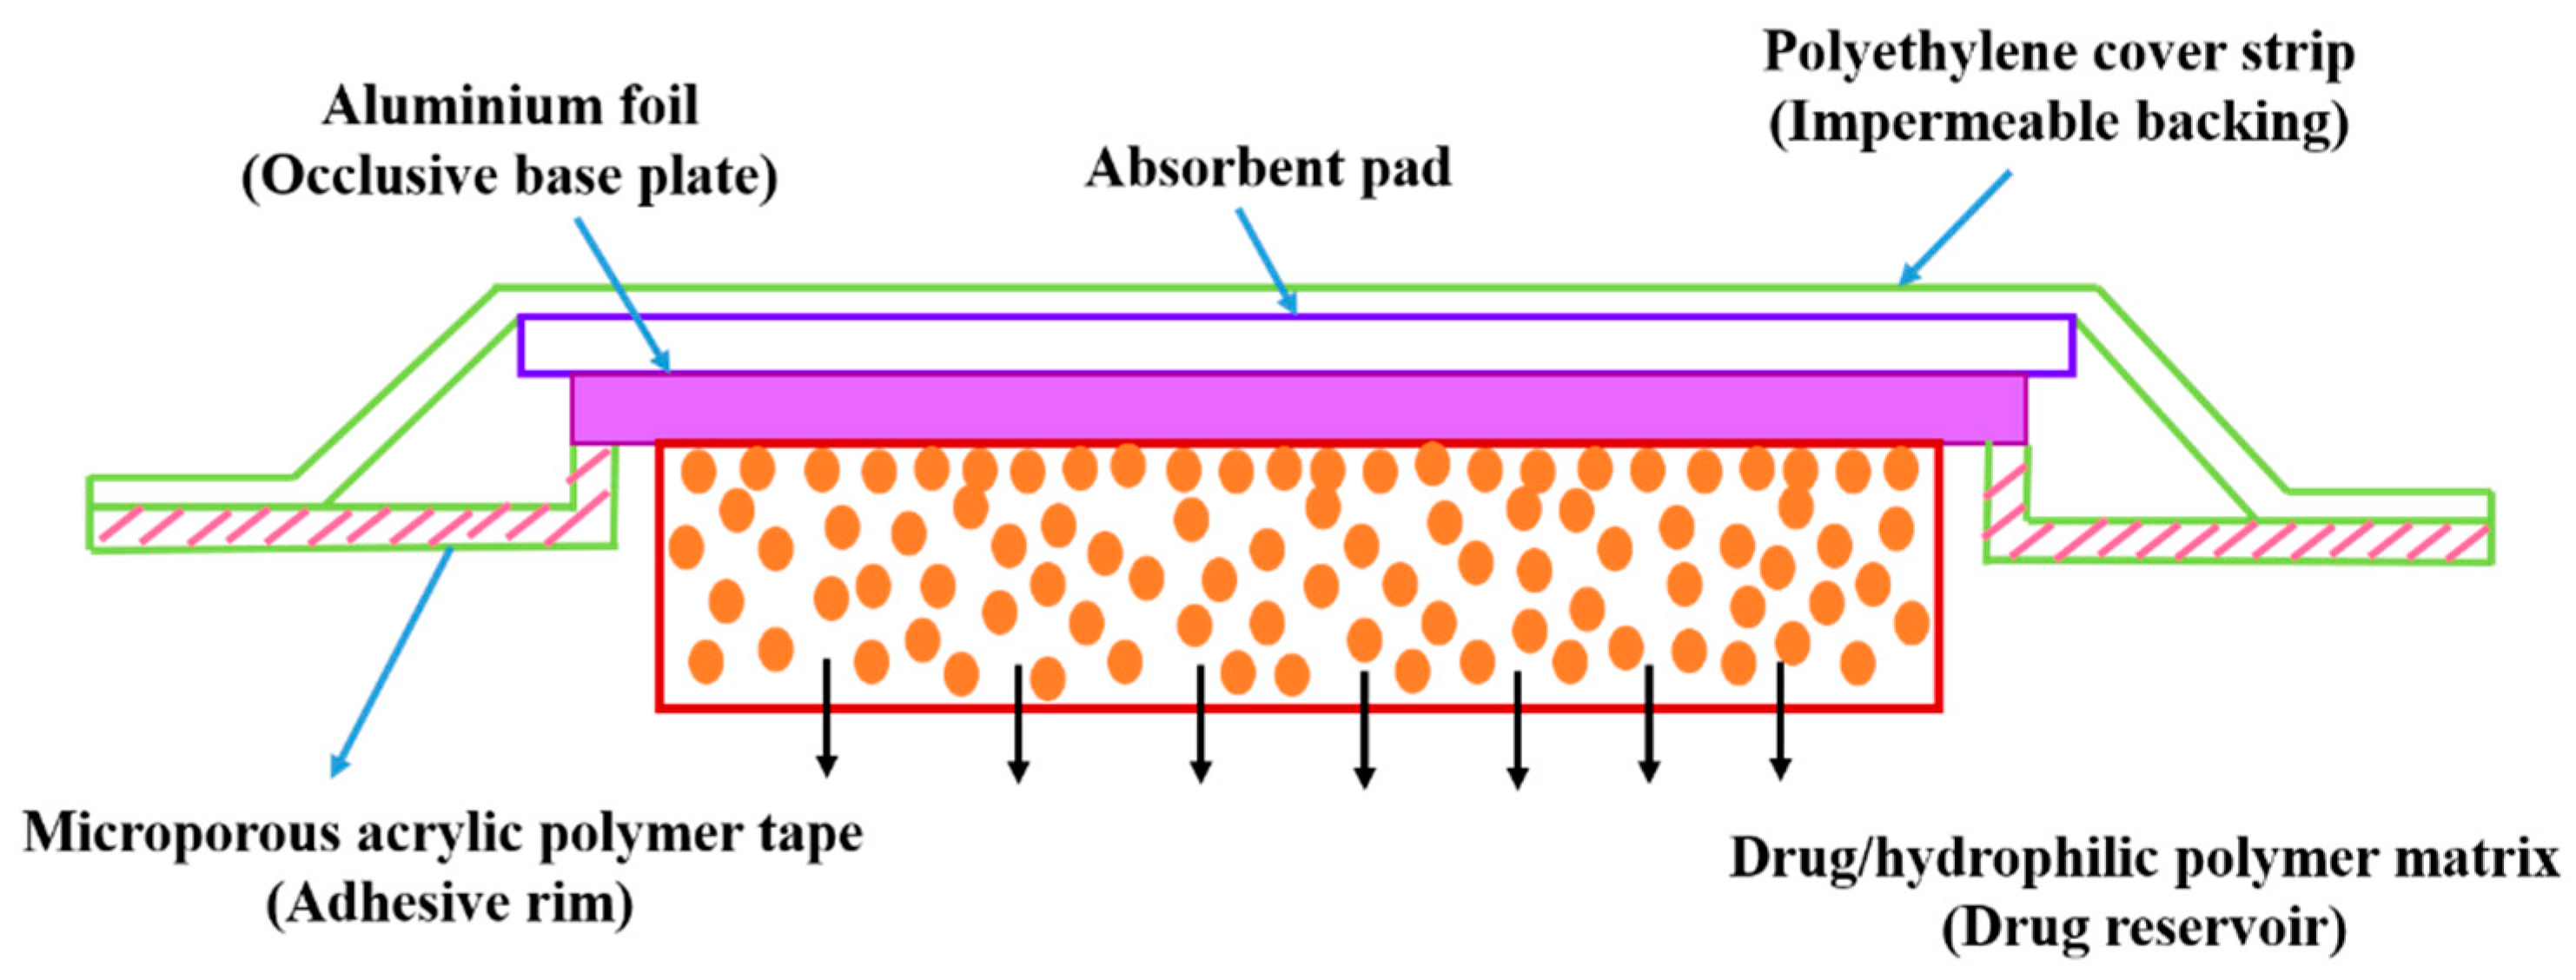

5.2.6. Nitro-Dur System

- Yang, W.W.; Pierstorff, E. Reservoir-based polymer drug delivery systems. J. Lab. Autom. 2012, 17, 50–58. [Google Scholar] [CrossRef]